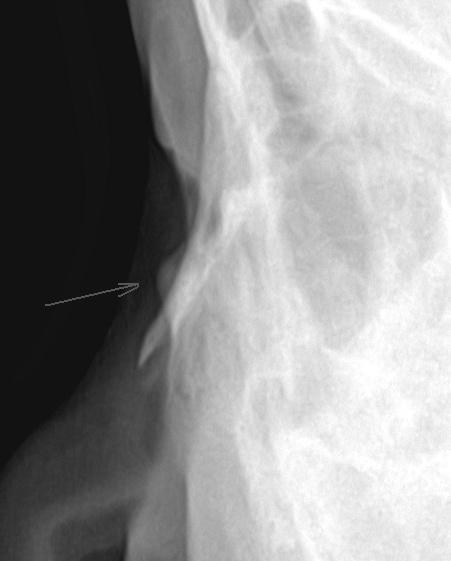

m 13y 曾打架时被人用砖砸到鼻骨左侧。该处可触到硬性肿物,请老师们给个意见...左侧近板鼻骨侧位。

未见明显骨折征像,箭头所示为软组织包块,可能是骨膜下血肿所致

可能为1、颧骨重叠可能性大。2、鼻骨骨膜血肿钙化/骨化可能性小3、上颌骨骨瘤不除外。建议加照颅骨正位片,必要时ct检查。

此鼻骨片子不是纯侧位,考虑颧骨重叠可能性大。

软组织密度影,考虑为外伤后皮下结缔增生改变,建议ct检查。

鼻骨未见明显骨折征像,考虑颧骨重叠可能,建议ct进一步检查。

肯定不是颧骨重叠影,人家已经摸的到肿块了!!!